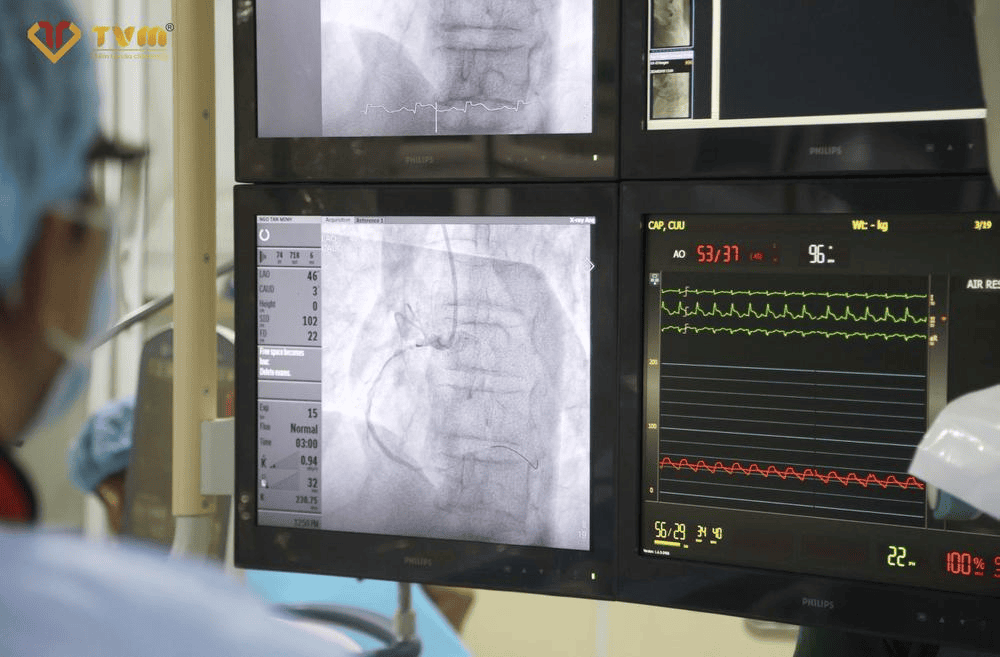

Trung tâm tim mạch Bệnh viện Đa khoa Thanh Vũ Medic Bạc Liêu tự hào là đơn vị đầu tiên của tỉnh Bạc Liêu áp dụng các công nghệ và kỹ thuật tiên tiến trong điều trị tim mạch được chuyển giao từ bệnh viện Chợ Rẫy. Hệ thống phòng mổ đạt chuẩn Anh Quốc cùng với các thiết bị chẩn đoán hình ảnh hiện đại như Hệ thống DSA - chụp mạch máu xóa nền, máy chụp MRI 3.0 Tesla,  máy chụp mạch vành CT đa lát cắt và máy siêu âm tim 4D, giúp chúng tôi chẩn đoán và can thiệp chính xác, hiệu quả hơn. Những kỹ thuật can thiệp mới như đặt stent động mạch vành hay can thiệp mạch vành qua da là phương pháp ít xâm lấn, giúp bệnh nhân mau hồi phục và tránh được những cuộc mổ hở đau đớn.